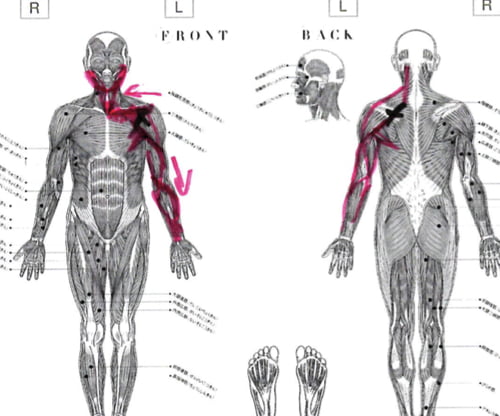

実際にお身体の状態を診させて頂くとこんな感じでした。

Xは痛みの場所。赤い線は筋肉や腱の硬直やヨジレ。

顎下から鎖骨、そして肘に向かうラインに硬直やヨジレが集中しています。

そして首の後ろ側は脇の辺りまで硬直。

腕の上がり方を見てみると、真上のは上がらないものの

肩の関節には異常が無いようです。

肩関節周りの癒着も無いようですので

肘や脇、鎖骨、胸付近の筋肉が硬直していて

腕を上げる際に伸び代が無く、腕が上げられない。

そう考えていいと思います。